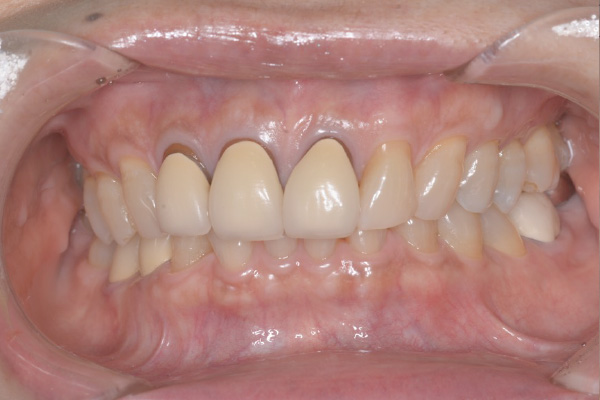

Case.03

インプラントの症例 インプラントの症例

治療前〜治療後のレントゲン写真

患者様の要望過去に治療したブリッジを外し咬み合わせの平面を整えて、被せ物や詰め物を綺麗にしたい。

治療期間10ヶ月

治療費用約1,600,000円

治療内容インプラント2本、アンカースクリューを用いた部分矯正、

セラミックによる補綴治療

治療のリスクセラミックの破折の

可能性